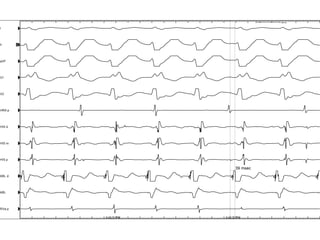

¿Tipo de taquiarritmia?

A.  Taquicardia sinusal

B.  Taquicardia por reentrada nodal AV

C.  Taquicardia por reentrada AV (por HPE)

D.  Fibrilación auricular con respuesta ventricular

rápida

Taquicardia	sinusal

TRAV

TRNAV

AC	x	FA